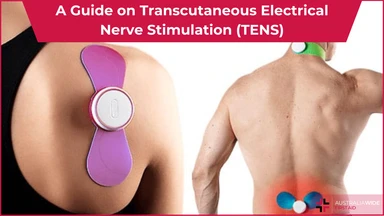

Transcutaneous Electrical Nerve Stimulation (TENS) is a therapeutic method of pain relief. It utilises an electrical device that emits electrical currents and streams the impulses via electrode patches attached to the skin.